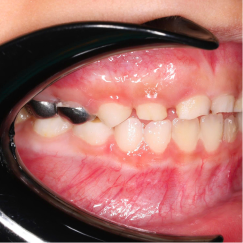

SSC (Stainless Steel Crown) là mão răng bằng thép không gỉ, được thiết kế sẵn với nhiều kích cỡ khác nhau, thường dùng để phục hồi răng sữa đã bị sâu lớn hoặc tổn thương nặng. Đây là một dạng phục hình toàn phần bao phủ toàn bộ thân răng, giúp bảo tồn và duy trì chức năng của răng sữa cho đến khi thay răng vĩnh viễn.

- Bảo vệ răng sau điều trị tủy

Mão SSC giúp bao phủ toàn bộ thân răng, giảm nguy cơ nứt vỡ và tái nhiễm khuẩn.